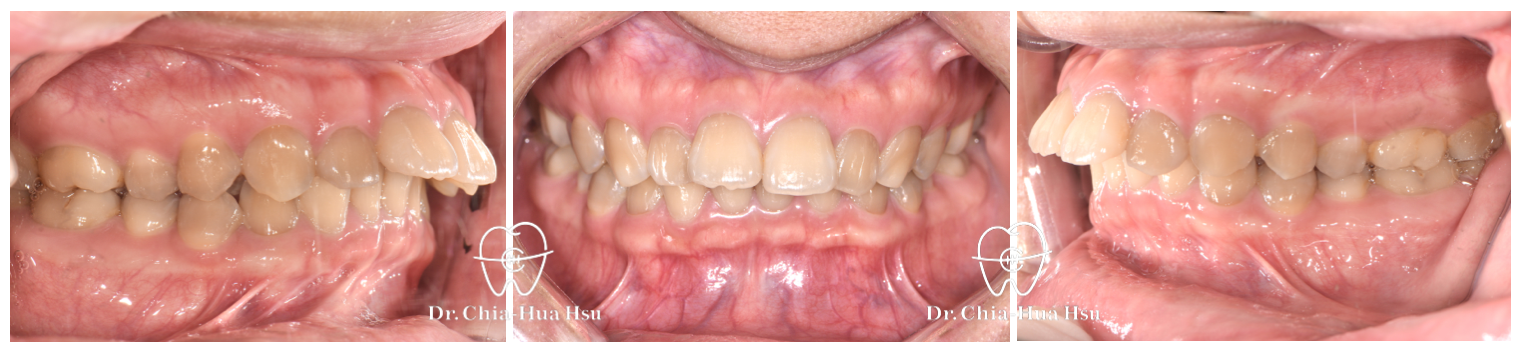

• 病患主訴:暴牙、嘴凸、深咬。

• 問題分析:患者是牙齒二類咬合(Skeletal Class II)、方臉型、暴牙以及齒列不整齊。

• 治療結果:齒列排齊,嘴凸改善,外觀變得更和諧,笑容也更有自信。

治療前

治療後